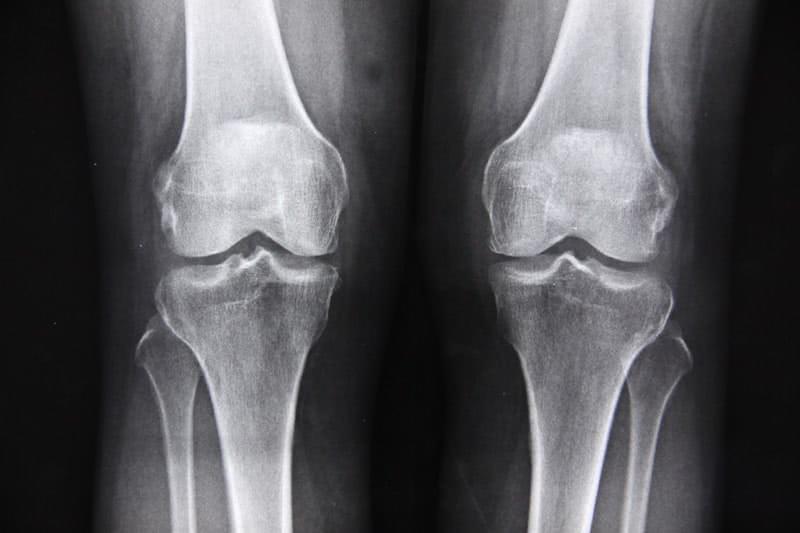

画像検査はレントゲンが主流です。ピロリン酸カルシウムの結晶が関節内の軟骨や半月板に沈着している場合、レントゲンではその石灰化が白く映し出されます。